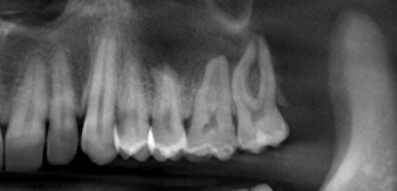

28-year-old man with a large lesion of the maxilla

A 28-year-old man was referred to the oral surgeon for a large lesion involving his left maxilla that the dentist noted in a panoramic film.